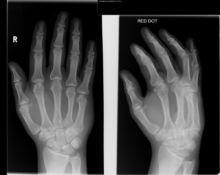

身體的其他關節出現骨頭錯位,很可能就會使支撐韌帶輕微或嚴重撕裂,從而發生關節變形,這就是由骨頭錯位引起的損傷。任何關節都可能受到扭傷,尤其是膝關節、踝關節以及手指關節,扭傷的關節功能依舊,但在使用時會很痛,並有腫脹和皮膚變色的現象,這是輕度扭傷。輕度扭傷不會有危險,但如果扭傷嚴重,所有支撐韌帶嚴重斷裂,就要去醫院了。

骨頭錯位● 及時檢查扭傷嚴重不妨對關節做x光照像檢查,因為嚴重扭傷與骨折經常不易區分。如確診,可在扭傷的肢體或手指部位鑄敷石膏模。